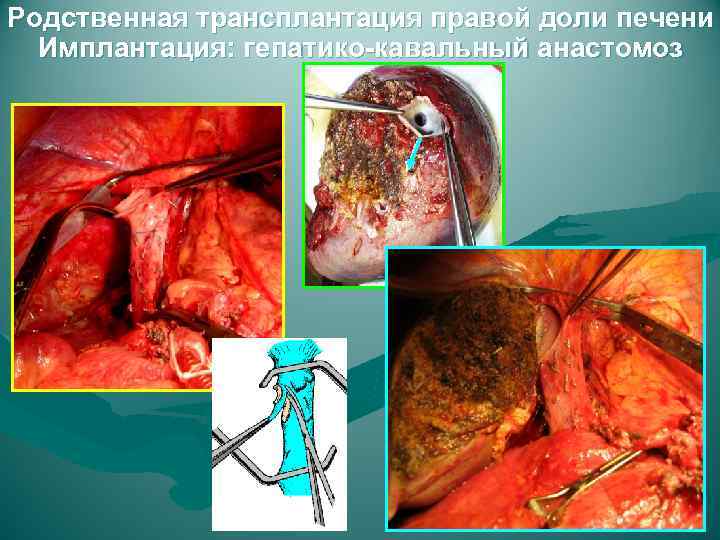

Родственная трансплантация правой доли печени Имплантация: гепатико-кавальный анастомоз

Родственная трансплантация правой доли печени Имплантация: гепатико-кавальный анастомоз